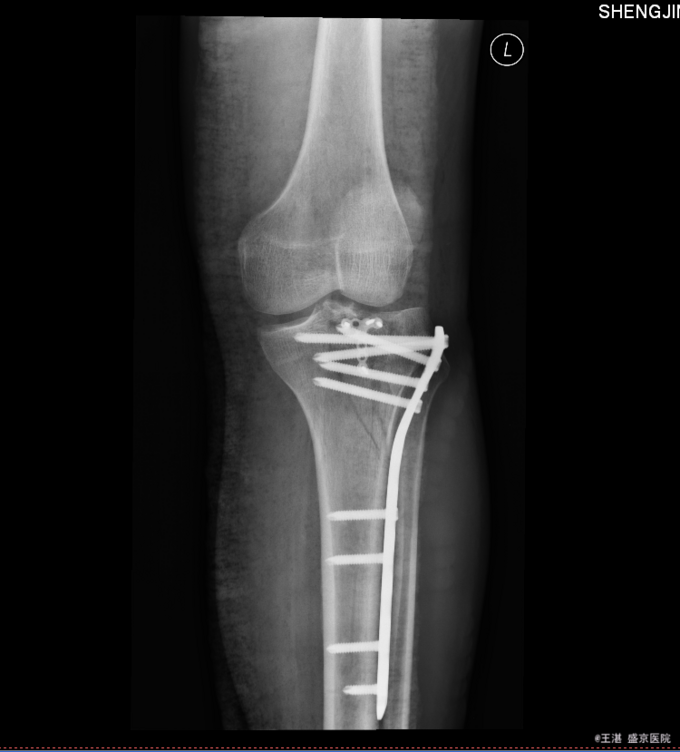

患者入院后完善相关检查,明确诊断,手术指征明确,于2015-12-2日于全麻下行左胫骨平台骨折切开复位内固定术,术后经抗炎、止疼等对症治疗后,患者恢复顺利,切口愈合良好,可出院。